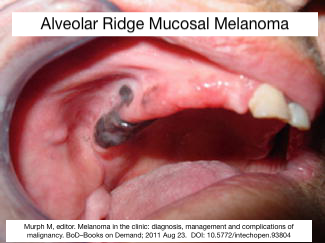

Melanoma can occur in Mucosal Sites like Rectum, Sinonasal, Vaginal Wall I always found this interesting because we usually associate it 🦀 with skin ☀️ Melanocytes are Neural Crest Derived 👶 and they migrate to the mucosa (as well as skin). #pathx #embryology #peds

Melanoma can occur in Mucosal Sites like Rectum, Sinonasal, Vaginal Wall I always found this interesting because we usually associate it 🦀 with skin ☀️ Melanocytes are Neural Crest Derived 👶 and they migrate to the mucosa (as well as skin). #pathx #embryology #peds